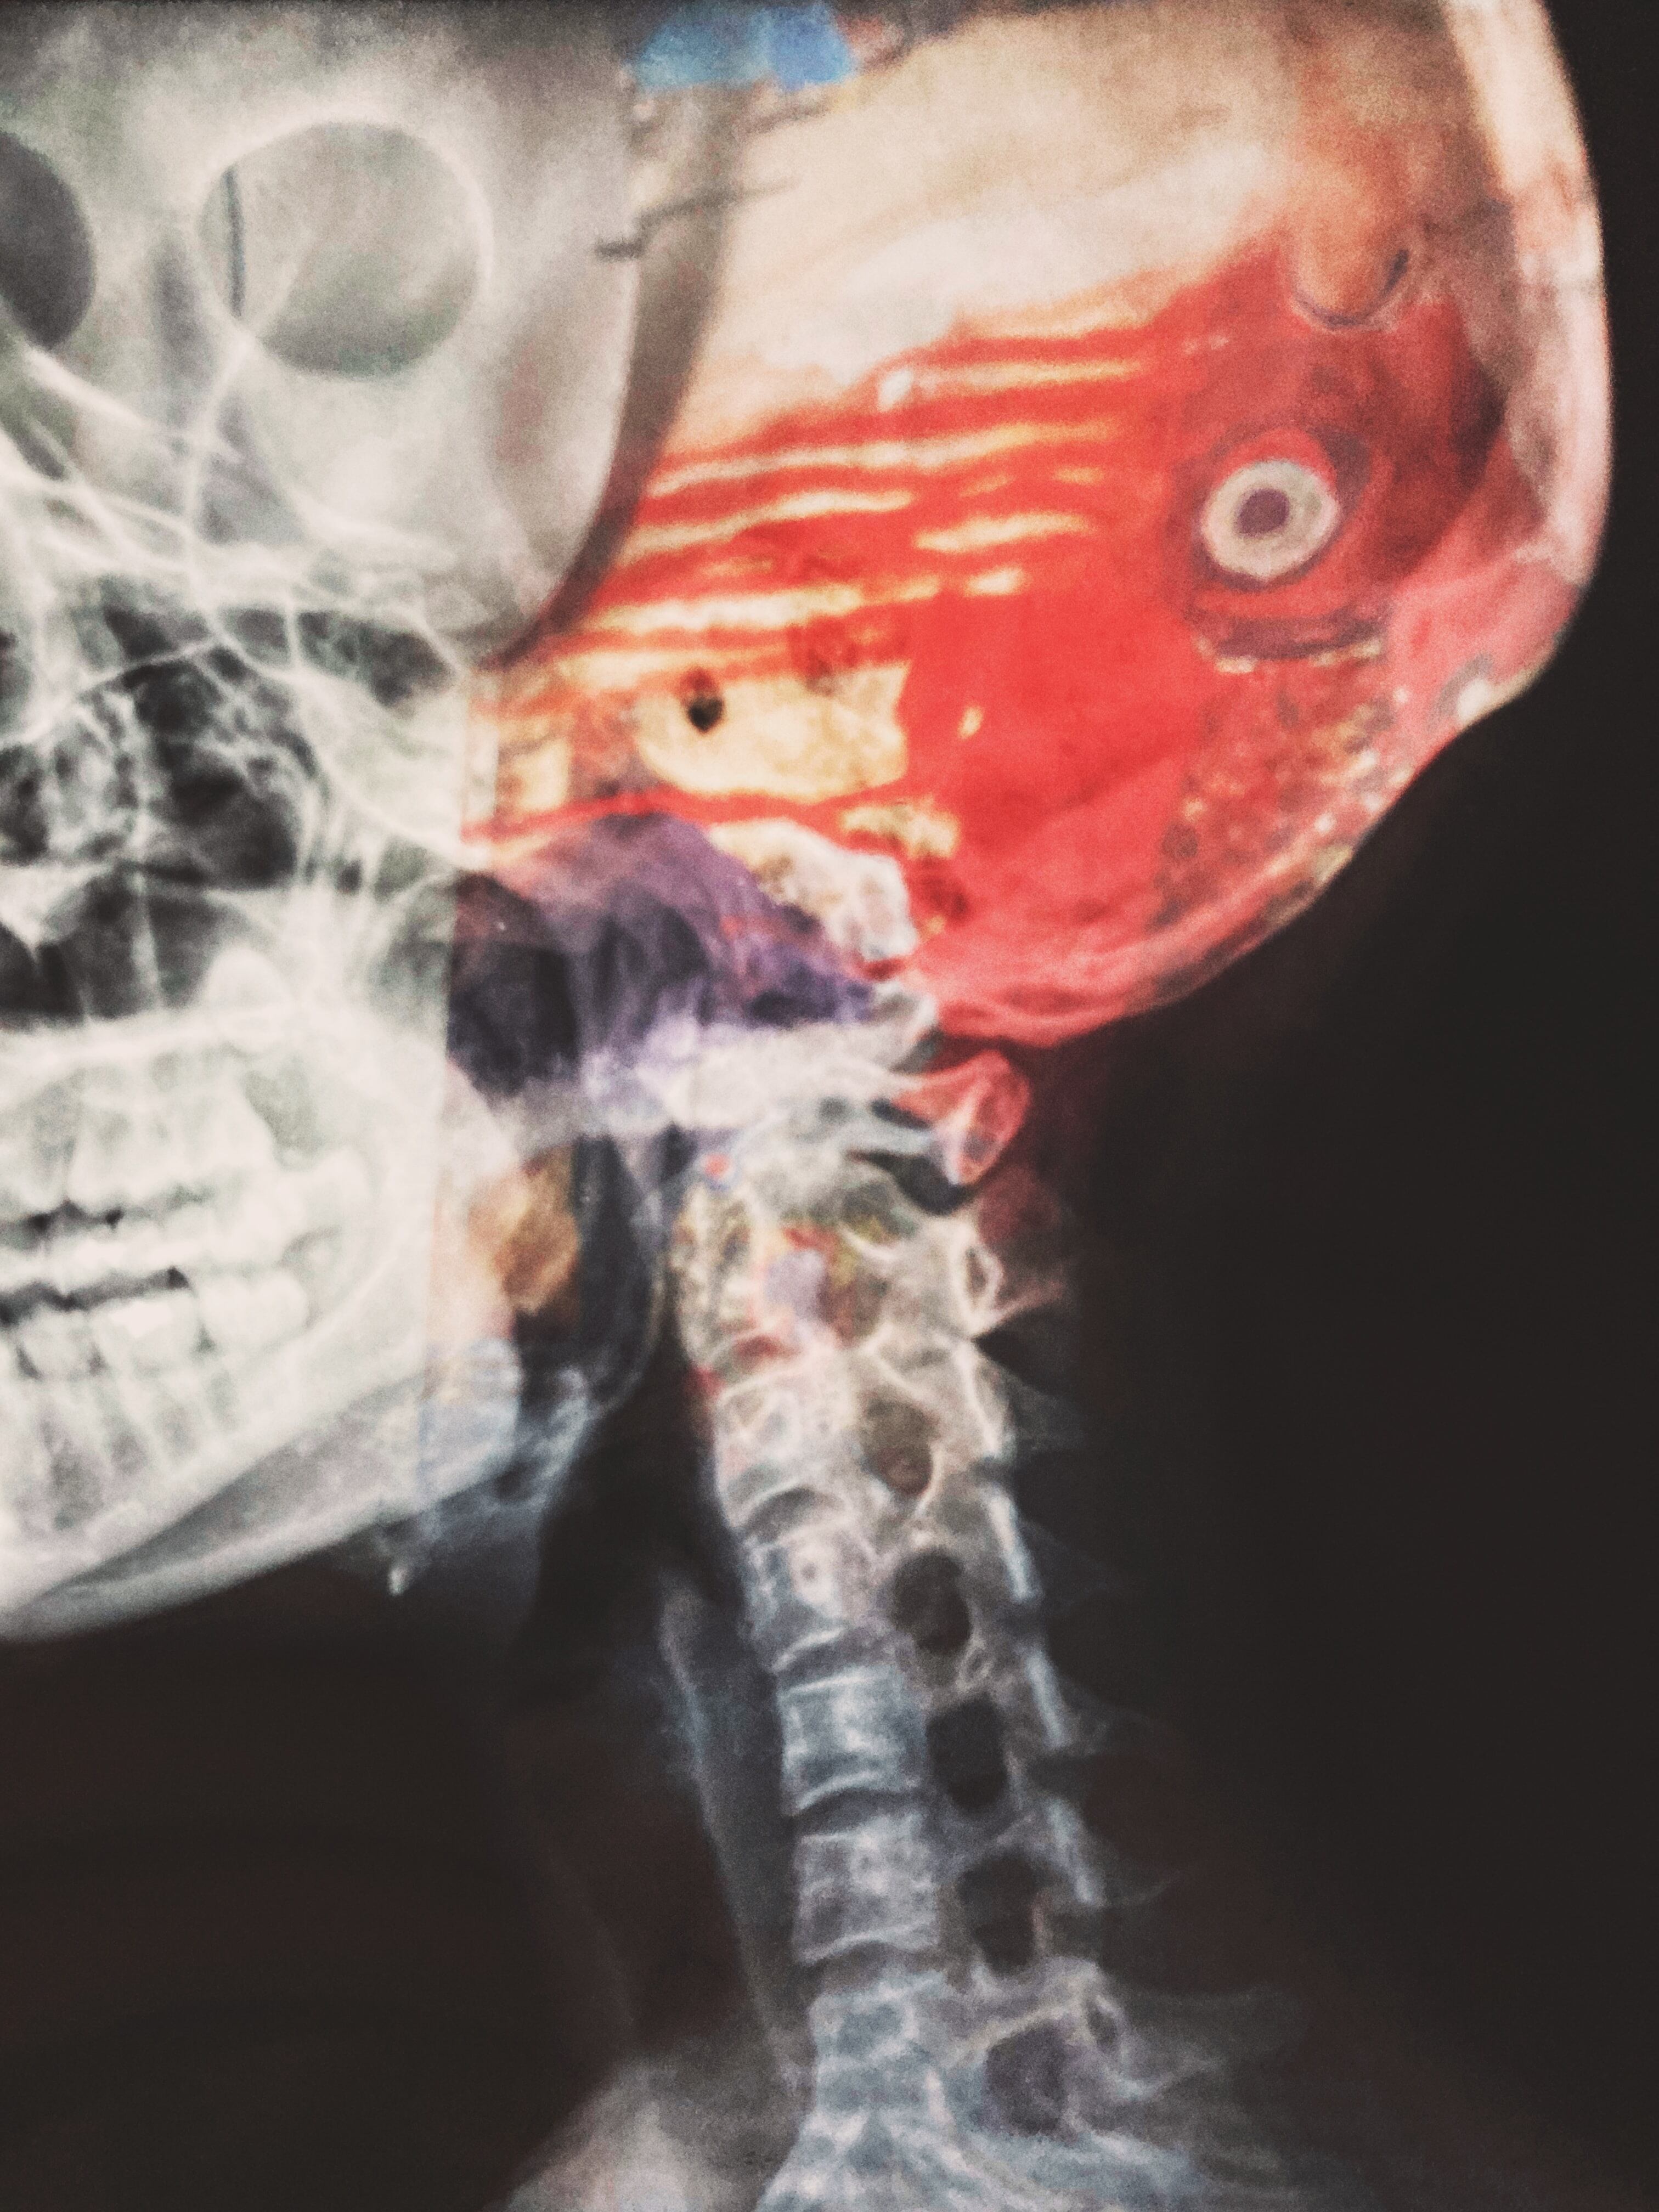

Resulta que luego de tomarse un par de radiografías para encontrar la causa del dolor de cuello, descubrió que tenía una bala enterrada.

Cuando las radiografías de su cuello estuvieron listas, Zhao He descubrió toda la verdad.

De acuerdo con el testimonio de Zhao He, la vieja bala enterrada en su cuello tendría unos 77 años ahí dentro.

“Pudo haber entrado por el lado izquierdo de la nariz, perforando la mandíbula superior y arrancándole los dientes antes de alojarse en el cuello.”

No obstante, por recomendación médica, tuvo que conservar la bala en su cuerpo porque “se encuentra cerca de algunos vasos sanguíneos importantes”.